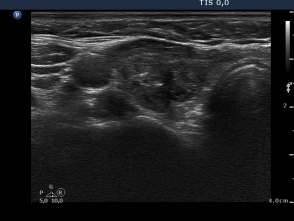

8 years after the sclerotherapy (fourth row of images):

Clinical presentation: the patient underwent regular follow-up examinations with yearly TSH and ultrasound examinations. The size of the nodule was always smaller than 50% of the original, pretreatment volume and the TSH was in the normal range.

Hormonal investigation indicated euthyroidism ( FT4 15.2 pM/L) with subnormal TSH (0.22 mIU/L).

Ultrasonography. The size of the nodule first ever in the follow-up period exceeded the 50% of the pretreatment size, it was 55.2%.

Suggestion: to continue the follow-up.